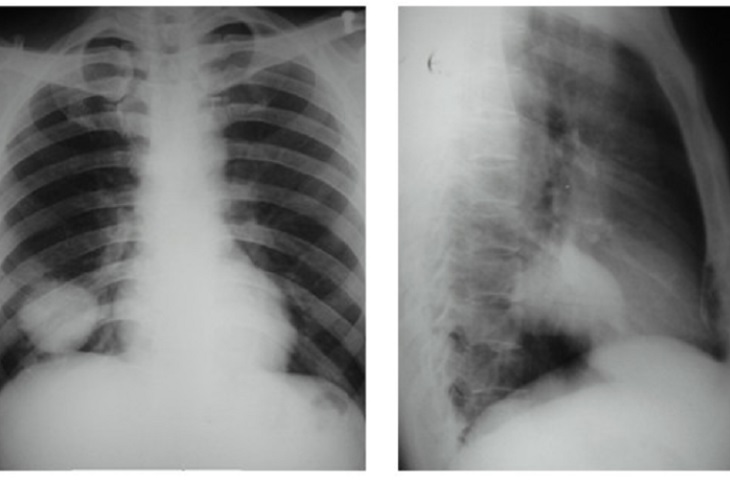

giảm đau ung thư Khối u ung thư quái ác chèn lên cơ quan lân cận của một người bệnh